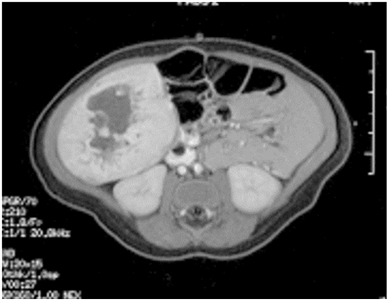

On MRI, vascular tumors of the liver are hyperintense on T2 imaging and hypointense on T1 imaging, with postcontrast imaging demonstrating early peripheral enhancement with eventual diffuse enhancement.[76] In practice, these tumors have been classified according to their clinical characteristics and radiological assessment.[76,154] In general, hepatic vascular tumors can be benign or malignant.

These lesions are usually divided into the following three categories:[76,154]